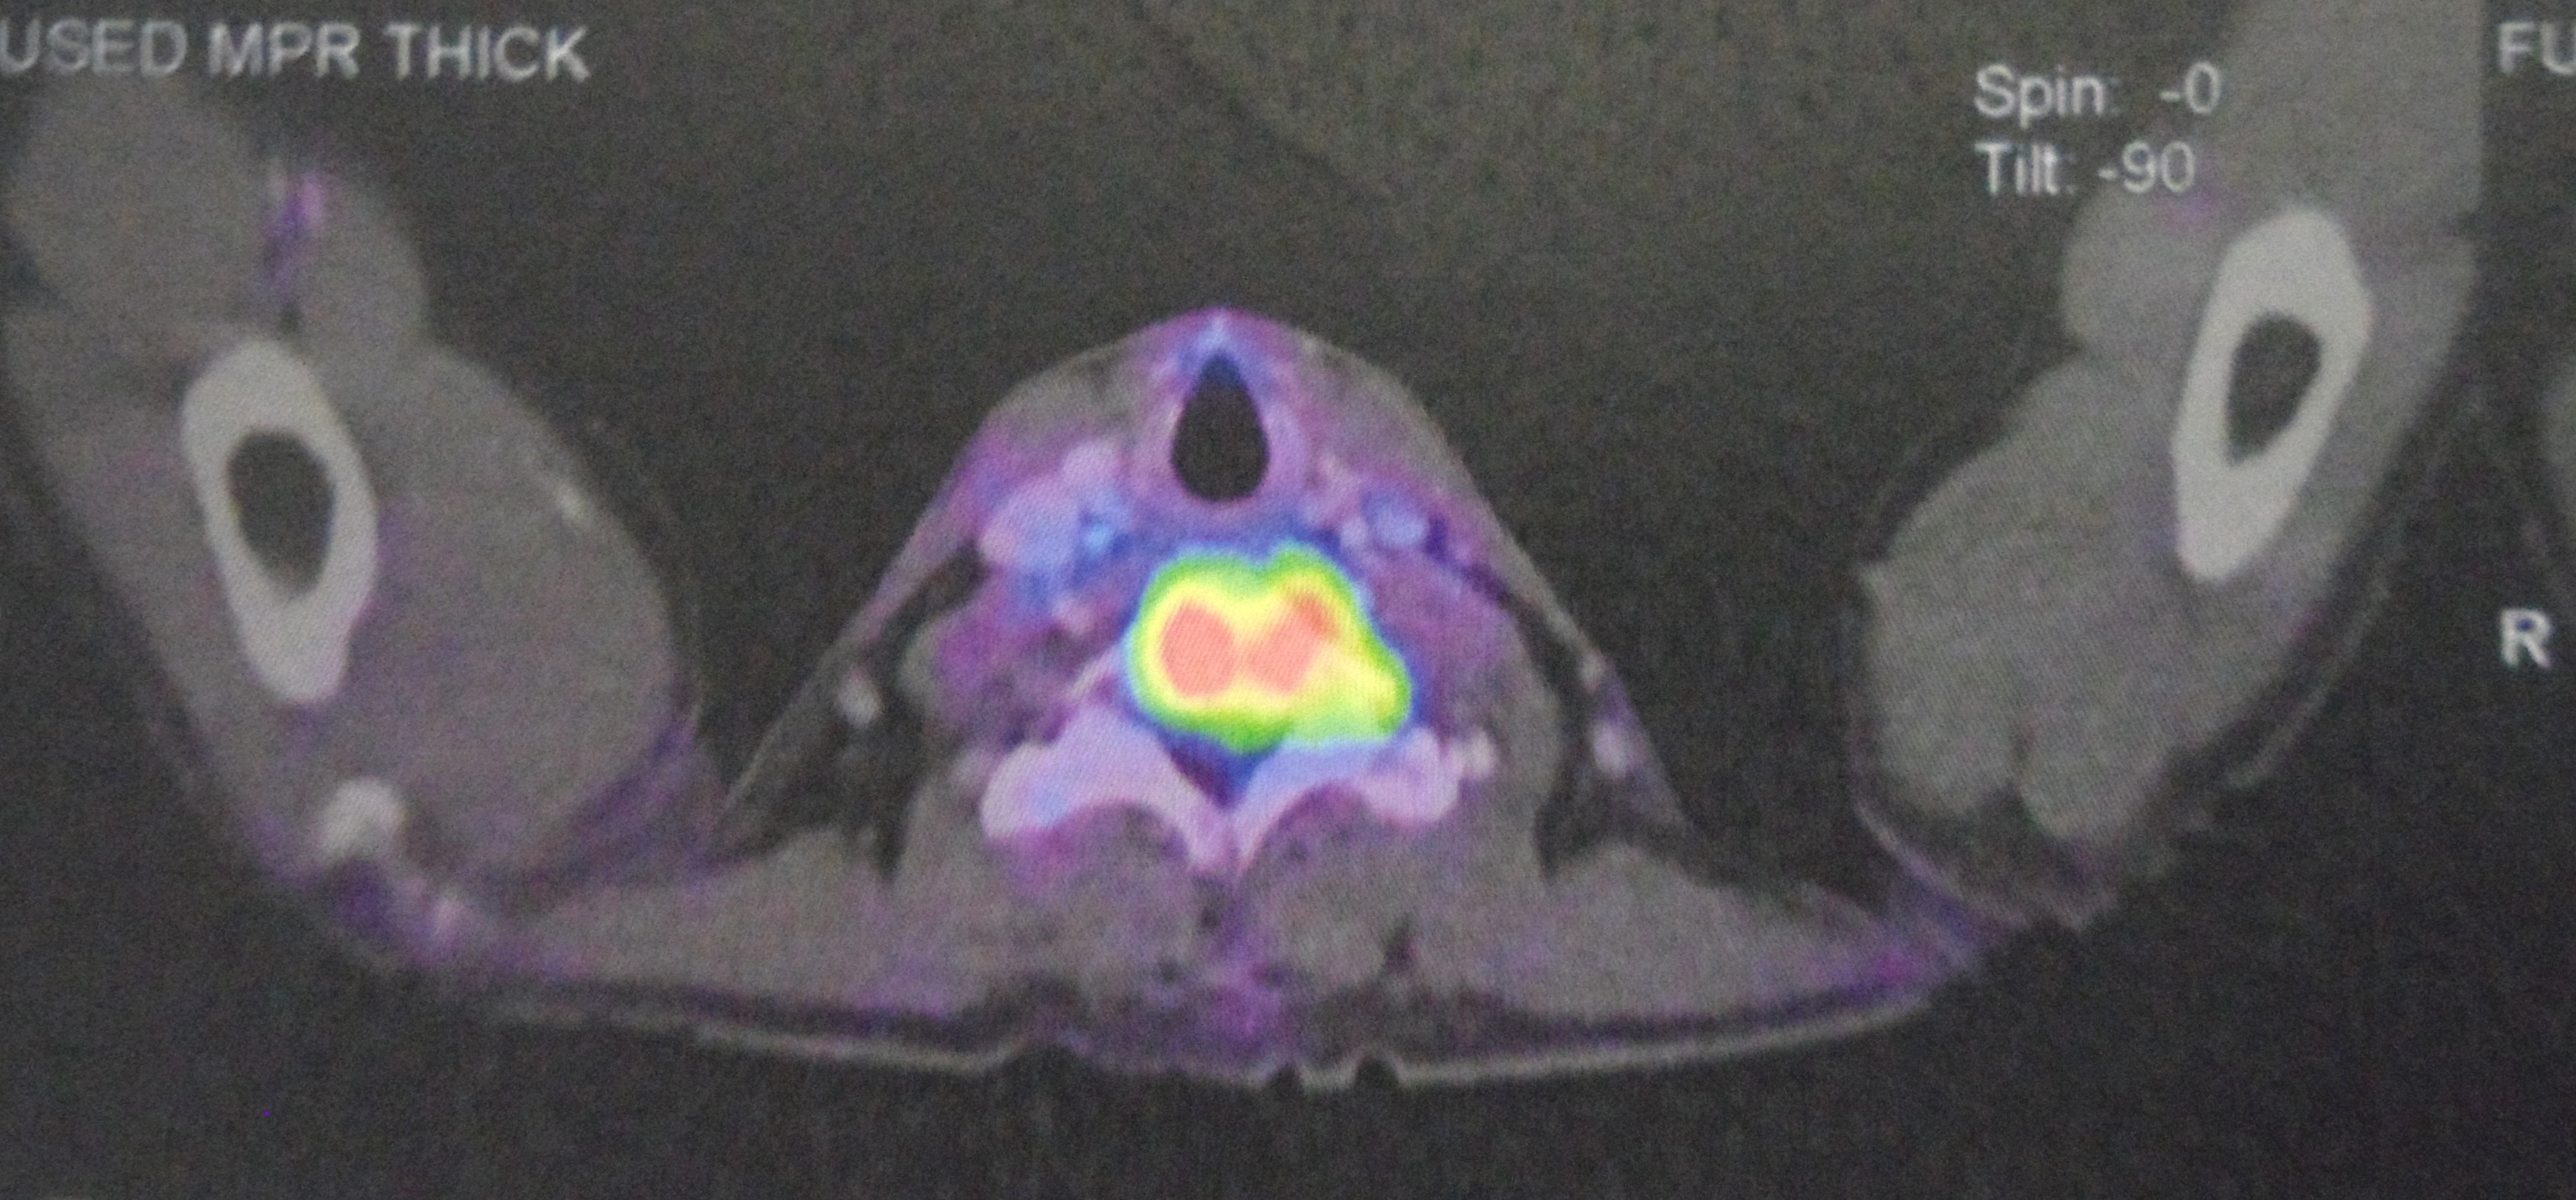

Study the three pictures below and compare them with the PET scan done on 10 August 2017 (above). You don’t need to be a doctor to know that PK is not getter better. He is getting worse and the cancer has spread more widely.

The PET scan report of 11 April 2018 stated the following:

- New development of large reticulonodular changes at the left upper lobe, probably related to post-radiation inflammation.

- New FDG avid mediastinal nodes, probably reactive nodes from inflammation.

- Metabolic increment in the left level IV cervical node.

- Mixed metabolic changes in the retroperitoneal and pelvic nodes.

- New development seen at thoracic stomach wall nodule and peri-bowel node at celiac axis, and celiac trunk nodes.